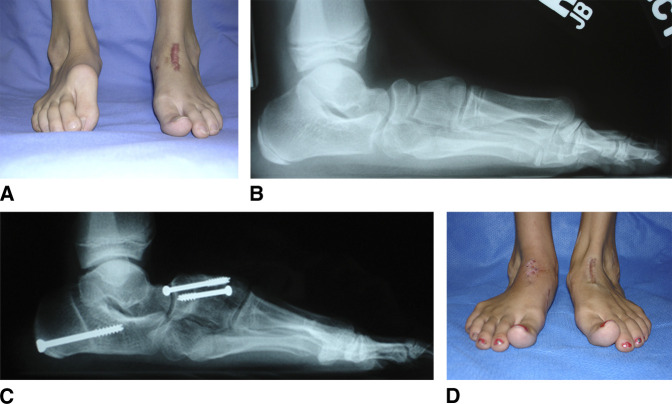

Figure 3.

Dorsal bunion. A–D, Preoperative and postoperative radiographs and clinical photographs of a 10-year-old girl with a history of bilateral congenital clubfoot treated with extensive soft-tissue releases at 6 months of age, who presented with bilateral dorsal bunion deformities. She was treated with a double bone-block fusion of the navicular-first cuneiform and first-second intercuneiform joints, anterior tibial tendon transfer to the second cuneiform, flexor hallucis brevis intramuscular lengthening, first metatarsophalangeal joint release and pinning, and flexor hallucis longus tendon transfer to the first metatarsal neck. The photographs illustrate the preoperative deformity on the right foot after left foot correction and postoperative correction of both feet.